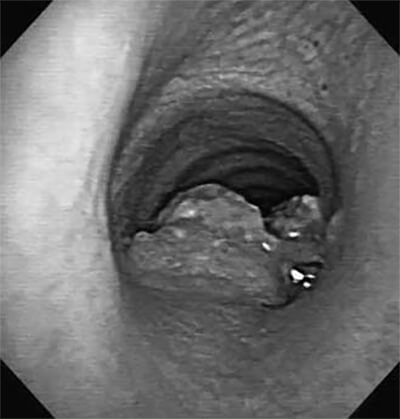

Η διάγνωση επιτυγχάνεται με βρογχοσκόπηση.

Με τη βρογχοσκόπηση μπορούμε να δούμε το εσωτερικό της τραχείας, να πάρουμε βιοψία και πληροφορίες για το σχεδιασμό του χειρουργείου.

Το εσωτερικό της τραχείας όπως φαίνεται σε βρογχοσκόπηση. Ο όγκος που αναπτύσσεται στο εσωτερικό της τραχείας αποφράσσει ένα μεγάλο τμήμα του αυλού της.